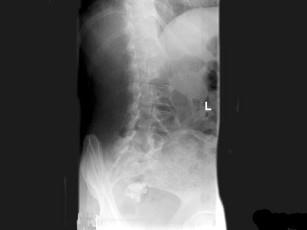

问题 女,47岁,腰背痛并向髋部和下肢放射,结合图像,最可能的诊断是?(?)

选项 A.腰5压缩性骨折 B.移行椎 C.脊椎裂 D.腰5椎弓峡部不连 E.Klipple-Feil综合征

答案 D